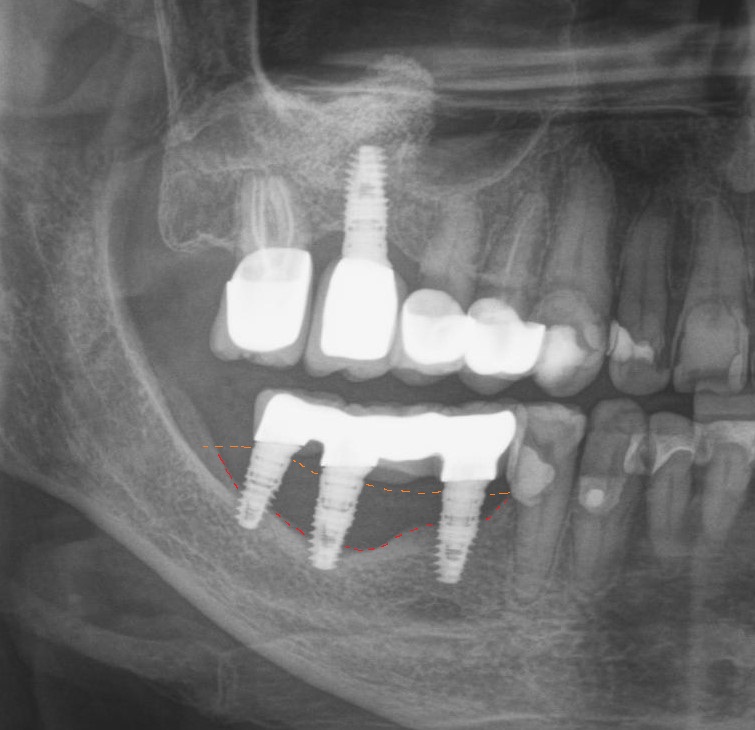

А так это выглядит на рентгеновском снимке

Как можно заметить, костная ткань не так сильно «пострадала», как в предыдущем случае (недокрученный формирователь десны на снимке слева был докручен).